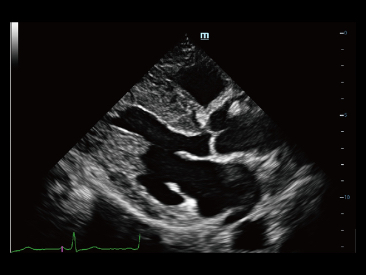

Desde que se fundó la compa?ía, Mindray ha explorado incansablemente nuevas formas de mejorar la confiabilidad del diagnóstico. Con la revolucionaria tecnología de ZONE Sonography?, la nueva plataforma ZST+ de Resona?7 lleva la calidad de la imagen por ecografía a un nivel superior mediante el procesamiento de datos de canal y la adquisición de zona.

Además de la calidad de imagen de primer nivel, Resona?7 también mejora las capacidades de investigación clínica con el revolucionario V?Flow para la evaluación hemodinámica vascular y con la adquisición de planos más inteligente a partir de conjuntos de datos 3D para el diagnóstico del SNC fetal. Al combinar el funcionamiento multitáctil basado en gestos más intuitivo y todas las características clínicas esenciales, Resona?7 realmente lidera las novedades en innovación de ecografías.